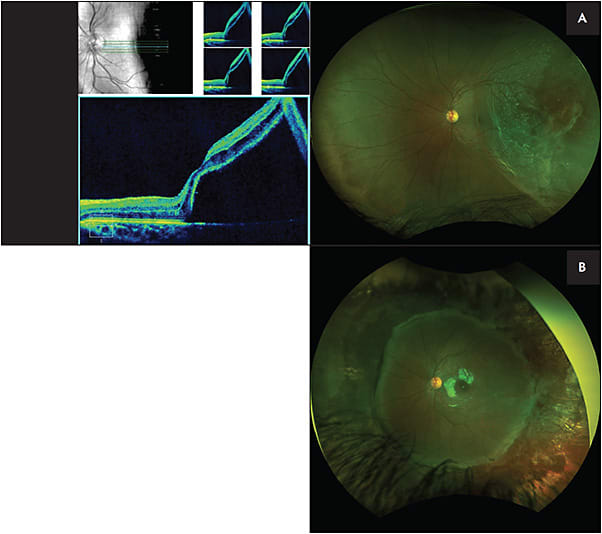

Initial treatment modalities include laser retinopexy, primary scleral buckle (SB), primary pars plana vitrectomy (PPV), and combined SB/PPV with or without lensectomy (Figures 1 and 2).41 The single-surgery success rate for all procedures in PRD repair has been estimated to be 73.3%. Reattachment rates generally are higher for traumatic etiologies and lower for congenital or developmental retinal anomalies.4,5,25 Among all forms of PRD, traumatic RD and RRD have a better anatomical success rate (78%) than TRD (39%). Despite a wide range of surgical approaches, PRD has a low surgical success rate of reattachment compared to adult RD.1,15 Even with successful anatomic reattachment, eyes are often at risk of amblyopia. Comanagement with a visual development specialist or pediatric ophthalmologist is essential to maximizing functional outcomes in the PRD patient.42